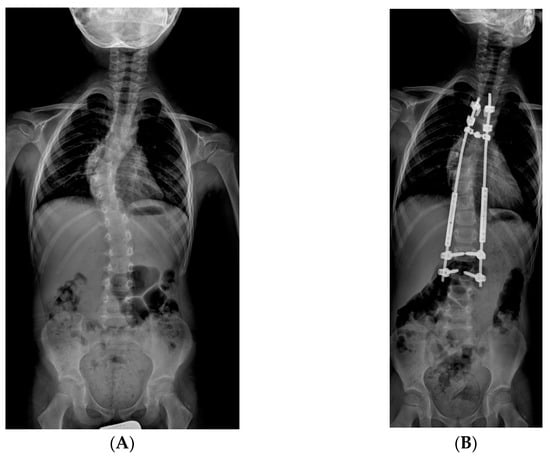

2.3.2. MCGR: Magnetically Controlled Growing Rods

3.2. Curve Correction